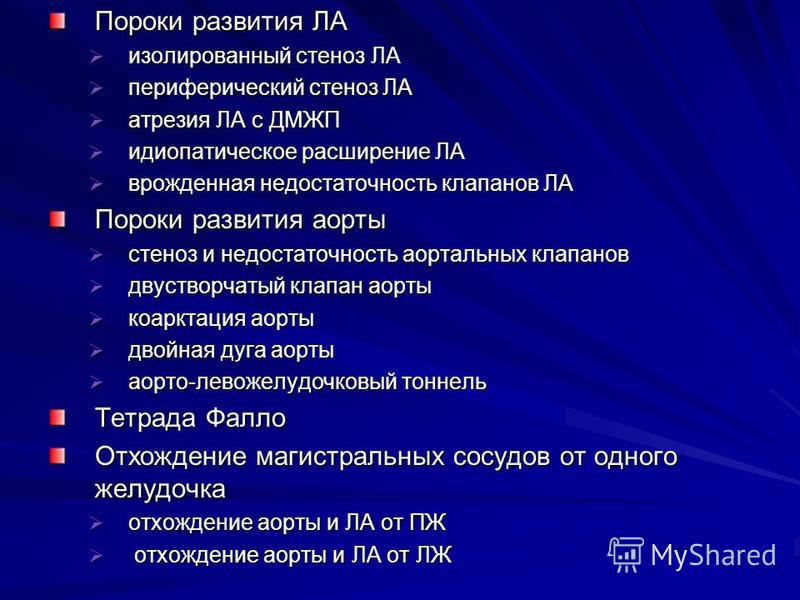

Фотографии и информация о приобретенных пороках сердца